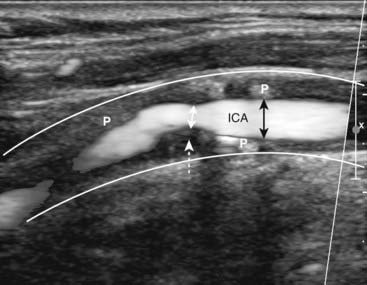

Figure 19-30 Normal proximal right internal carotid artery, duplex sonogram.

The upper display (dotted white arrow) depicts flow in the artery (the original displayed the flow in color). Within the white circle is the Doppler sampler volume, the measurements for which are shown on the lower graphical display, called the Doppler spectral waveform. The x axis represents time; the height of the waveforms represents the velocity of blood flow within the Doppler sampler volume. The velocity normally increases with each systole and decreases with each diastole.

imageCarotid stenosis begins to cause elevations in the velocity of flow when there is greater than 50% narrowing of the lumen. Significant stenosis alters the Doppler waveform proximal, at, and distal to the point of stenosis.

image Ultrasound is used to assess the thickness of the vessel wall (it gets thicker with atherosclerosis), the presence and nature of plaque, and analysis of the Doppler spectral waveform.

Figure 19-31 Stenotic right internal carotid artery, sagittal view.

The white lines indicate the normal location of the wall of the right internal carotid artery (ICA). The lumen is narrowed (double black arrows) due the presence of plaque (P) throughout the wall. At the site of the dotted white arrow, the lumen narrows to less than 50% of its normal diameter (double white arrow) from thicker plaque.